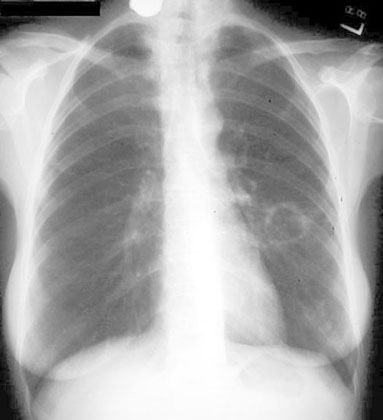

48 year old female presents with low grade fever, dry cough and 12 lbs weight loss in the past two months.

Findings:

• Thin walled cavity in left mid lung field

• No inflammatory response around cavity (unlike Tuberculosis)

Diagnosis

M Kansasii Infection